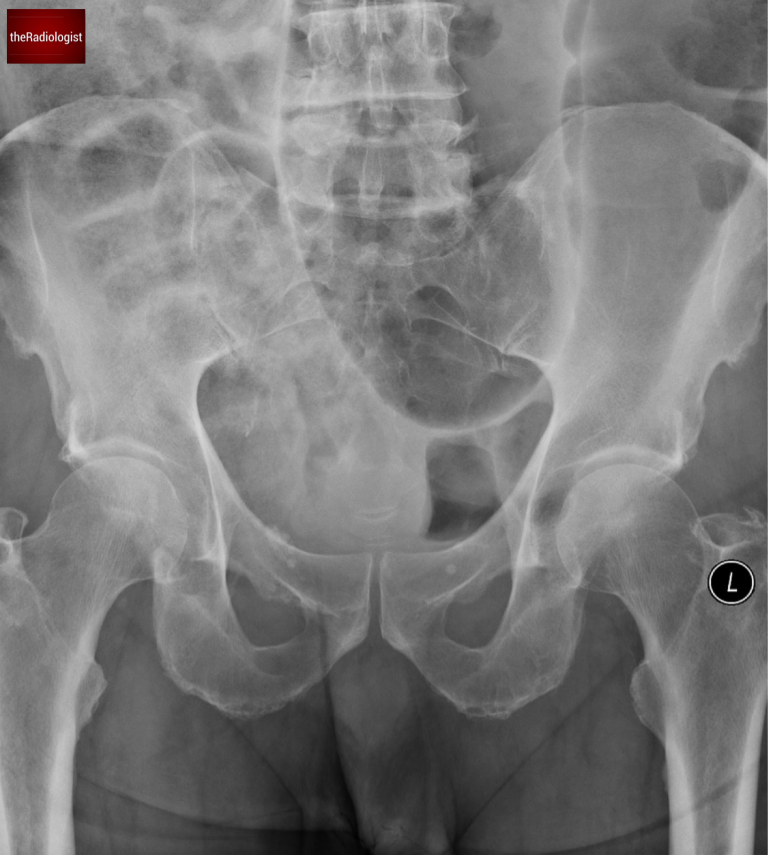

Let’s revisit the first X-ray. The single, dilated bowel loop has a coffee bean appearance—a classic but not entirely specific sign of sigmoid volvulus. The absence of haustra within this loop further supports the diagnosis of sigmoid volvulus.

The massively dilated bowel loop has the appearance of a coffee bean.